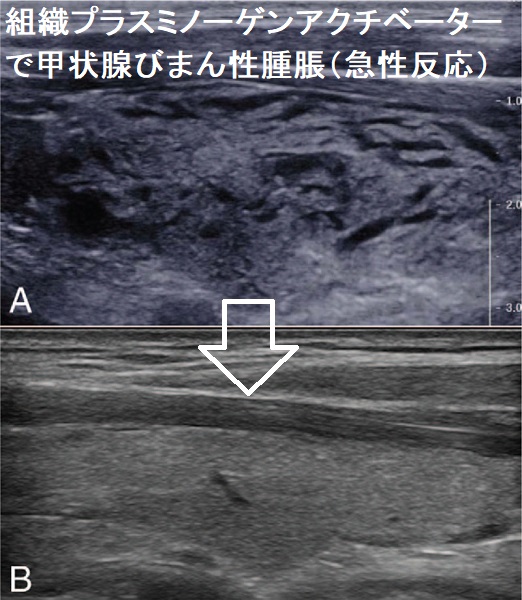

急性虚血性脳卒中(AIS)に対して、組織プラスミノーゲンアクチベーター(recombinant tissue plasminogen activator:rt-PA :アルテプラーゼ)による血栓溶解療法を行った後、

- 急激な甲状腺びまん性腫脹(急性反応、急性一過性甲状腺腫大));rt-PAはプラスミンを生成し、高分子キニノーゲンからブラジキニンを遊離させ、血管透過性が亢進するため。数時間後に回復。[Medicine (Baltimore). 2018 Sep;97(36):e12149.]

- 甲状腺内出血

急性呼吸不全を発症し気管内挿管。甲状腺腫瘤と甲状腺出血による気管圧排が原因で、後日甲状腺全摘術[Neurocrit Care. 2013 Dec;19(3):381-4.]

急性心筋梗塞での使用で発症[J Cardiovasc Med (Hagerstown). 2008 Sep;9(9):935-6.]

がおきる場合があります。